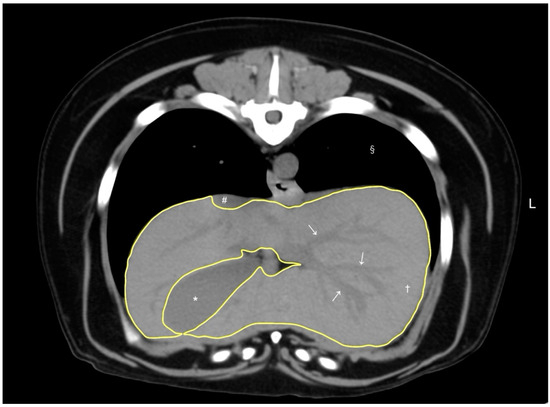

The median CT-based liver volume was calculated as 774.8 cm3 in dogs without hepatic disease (Table 1). There was a strong correlation (correlation coefficient, 0.81) between CT-based liver volume and body weight (p < 0.001, Figure 2) using Spearman’s rank correlation coefficient.

Figure 2. The correlation between CT-based liver volume (cm3) and body weight (kg). Each dot represents an individual dog. A strong positive correlation (Spearman’s rank correlation coefficient, rs = 0.81) was observed between liver volume and body weight, indicating that larger dogs tend to have larger liver volumes. The correlation was statistically significant (p < 0.001). The dotted line represents the trend line of the correlation.